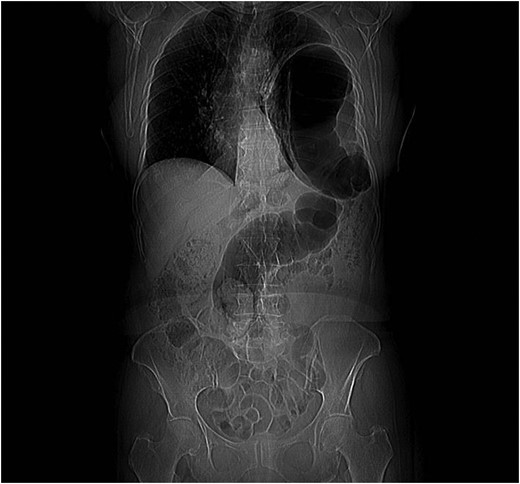

Thoraco-abdominal computed tomography (CT) showed the herniated bowel (transverse colon), translocated through a defect of about 7 cm in the left hemidiaphragm (Figs 2–4), a rightward deviation of the mediastinal structures and an atelectasis of the left lung (Fig. 5). The left colon had the appearance of a volvulus.

CT of chest showing defect on left side of the diaphragm and colon herniation in the thoracic cavity.